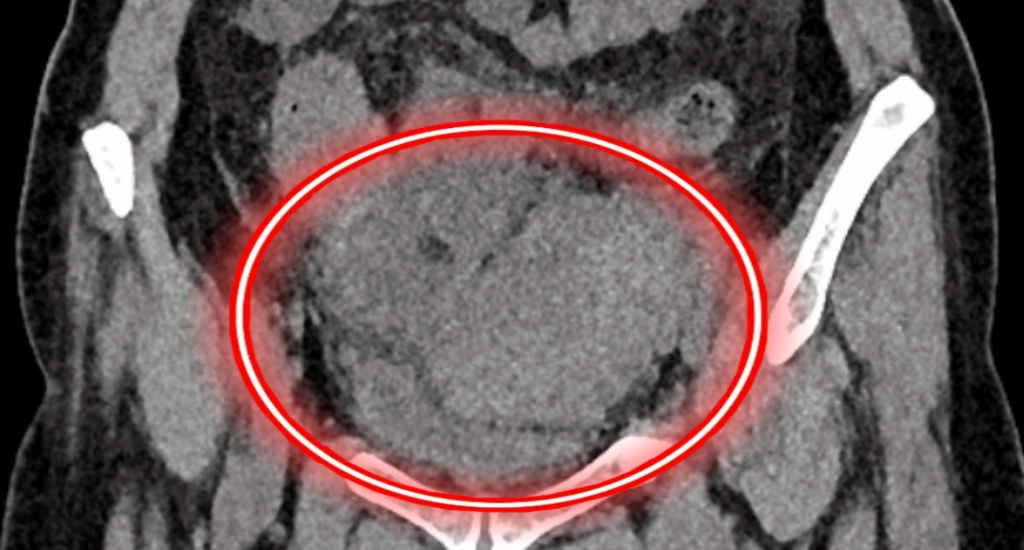

患者王女士今年53岁,因腹痛伴发热入院,彩超及血分析提示阑尾炎可能性大。普外科微创诊疗中心主任李鹏会诊后发现,患者下腹部触诊质硬,可触及明显肿块,建议行胃肠镜检查。此后,胃肠镜病理回示乙状结肠腺癌,全腹CT提示,结合病理学检查,符合乙状结肠肿瘤并瘤周脓肿、脂膜炎、多发淋巴结转移表现。

因患者乙状结肠肿瘤巨大,与膀胱、小肠、直肠及周围神经、血管紧贴,保留膀胱及直肠的难度大,肿瘤侵及子宫概率极大,需同时行子宫及其附件切除术,手术难度极大,风险极高。随后,经普外科微创诊疗中心、妇科、消化内科多学科讨论,根据患者自身情况及特点,制定了完善的个性化手术方案,尽最大可能完整干净切除肿瘤组织,减少正常组织损伤。